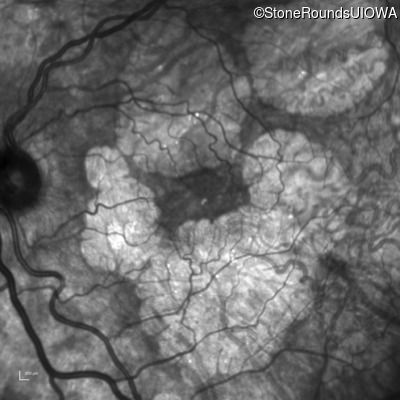

Infrared Fundus Photograph - Right - 20/20 -3

Exemplar